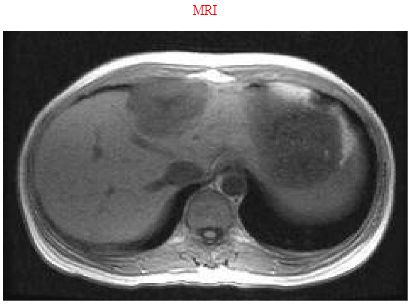

15. 一位41歲婦人,因兩個月前在健檢中心中被診斷出有肝腫瘤而就診。她因年逾不惑而做例行健診並無症狀。在先前的健檢中,已知肝功能完全正常,沒有B型或C型肝炎。她平常使用口服避孕藥。身體檢查無異常發現。在本院安排MRI檢查,報告是血管瘤(cavernous hemangioma) 如附圖一及圖二 ,大小與先前報告相同。以下建議何者最適當? (A) 追蹤檢查,使用CT或MRI,每3個月定期追蹤 (B) 排定時間做切片檢查以確定診斷 (C) 定期以胎兒蛋白αFP抽血追蹤 (D) 停用口服避孕藥 (E) 勸病人安心,不需再做進一步檢查